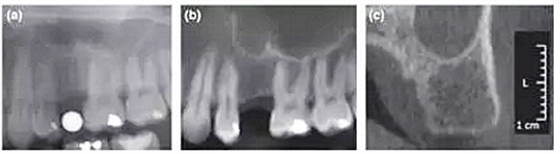

本研究共納入71名患者,所有擬種植位點(diǎn)行數(shù)字化全景(D-PAN)及錐束CT(CBCT)檢查。攝全景片時(shí),將一直徑5 mm的金屬球置于缺牙區(qū)。重組CBCT數(shù)據(jù)組分別構(gòu)建10 mm層厚的CBCT全景圖像(CBCT-pan)及1 mm層厚的斷面影像(CBCT-cross)。三名測(cè)量者在顯示器上應(yīng)用專(zhuān)業(yè)軟件測(cè)量圖像,在擬種植位點(diǎn)放置4個(gè)參考點(diǎn)以模擬種植體外形。分析比較根據(jù)3種影像選擇的種植體長(zhǎng)度和直徑的差異。并且針對(duì)每種種植系統(tǒng),比較根據(jù)CBCT-cross與其他2種方式(D-PAN和CBCT-pan)選擇的種植體尺寸。

結(jié)果顯示,根據(jù)CBCT-cross選擇的種植體(3個(gè)觀(guān)察者取平均值)比D-PAN和CBCTpan選擇的種植體直徑更小。在前磨牙區(qū)域,D-PAN和CBCT-pan選擇的種植體直徑也有顯著差異。相比D-PAN,CBCT-cross選擇的種植體顯著更短。在前磨牙位點(diǎn),3種測(cè)量方式選擇的種植體長(zhǎng)度無(wú)顯著差異。CBCT-cross選擇的種植體尺寸級(jí)別相比D-PAN和CBCT-pan無(wú)顯著差異。

總結(jié)來(lái)說(shuō),本研究的結(jié)果表明利用CBCT重建全景片與CBCT斷層影像選擇的種植體尺寸存在差異。在大多數(shù)病例中,相比全景片或CBCT重建全景片,根據(jù)CBCT斷層影像測(cè)量并選擇的種植體直徑和長(zhǎng)度均更小。